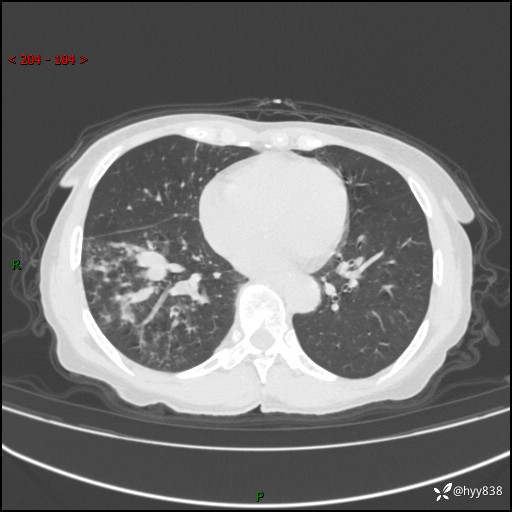

患者性别:男

患者年龄:69岁

简要病史:咳嗽咳痰2月,夜间加重

临床诊断:感染

胸部CT平扫